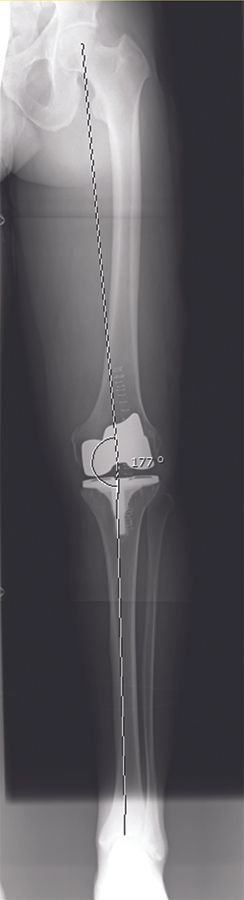

Approximately 600 patients were operated in our clinic with the balanced gap technique presented in this paper. In this patient cohort, the HKA changed from -6.7° ± 3.6° (range, -0.5 to -19°) preoperatively to -2.9° ± 2.1° (range, -0.5 to -5.5°) postoperatively. Hence, a residual varus was seen in all patients (Figures 15 - 16).

Furthermore, we conducted a randomized clinical trial in which we compared 75 patients operated with a standard MA technique with our adjusted MA technique. Baseline characteristics of the patients are presented in Table 1.

Postoperatively, all patients were assessed using the Knee Society Score [10], the Forgotten Joint Score [11], and the High Flexion Knee Score [12].

All patients were assessed preoperatively and at 24 months follow-up. There were no revisions in any study group, and all patients attended final follow-up. Clinical results are presented in Table 2.